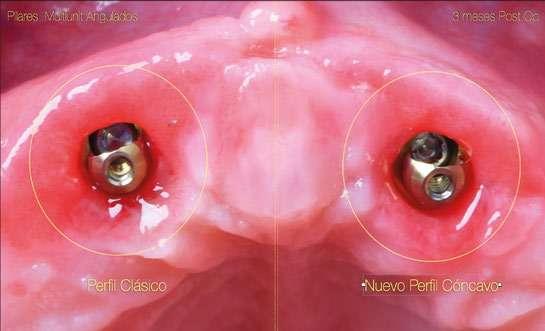

el área subgingival. (Refs.8,9,10). La finalidad del concepto es proporcionar el máximo espacio horizontal para el crecimiento de tejido conectivo supracrestal alrededor de la interfase de titanio o pilar personalizado ofreciendo protección al implante a costa de maximizar el grosor y estabilidad a las estructuras del fenotipo periimplantario (Ref.11). El verdadero reto surge en situaciones en las que es posible crear una prótesis múltiple del tipo FP1 (Ref.12), donde siempre se debe utilizar un pilar Multi-unit. Cuando se utiliza un implante asociado a este tipo de pilar para crear una emergencia natural desde la encía, éste se debe planificar teniendo en cuenta que el volumen del pilar va a ocupar prácticamente toda el área de la altura de tejido supracrestal (“Suprecrestal tissue height” Ref. 11) y debe estar “camuflado” en dicha zona de transición ocupando gran parte del espacio para el tejido conectivo supracrestal y del perfil de emergencia de la restauración (Ref. 13). Ya sea un pilar recto o angulado, debido a sus formas robustas y perfiles anchos, resulta difícil de planificar su colocación en zonas estéticas ya que el complejo implante-pilar se va a comportar como un implante tipo “tissue level” (Ref.14) (Fig.1). Con los diseños clásicos de pilares no se van a poder respetar las concavidades subgingivales deseadas y siempre va a implicar la eliminación de hueso, sobre todo a nivel interproximal y vestibular en la zona del cenit del diente (Ref.15) (Fig.2). Las consecuencias automáticas serán picos de hueso interproximales reducidos, papilas más cortas y dientes con cenits más planos y anchos en el tercio gingival. Incluso en situaciones de implantes adyacentes puede provocar la pérdida o ausencia total de papila interimplantaria (Ref.7) (Fig.3).

Debido a esta compleja situación, se ha desarrollado una nueva línea de pilares Multi-unit que rompe con los diseños clásicos y que se presenta a continuación: (Figs. 4,5).

Con respecto al Multi-unit recto, su principal característica es la emergencia desde la plataforma del implante con un perfil completamente cóncavo. Por una parte, va a maximizar el efecto de “cambio de plataforma” en su parte más crestal a nivel de la plataforma del implante y por otra va a facilitar mucho más espacio para la creación de tejido conectivo supracrestal a lo largo de toda la transición hasta la plataforma restauradora. El perfil cóncavo

del pilar también respetará en mayor medida los espacios comprendidos entre el pilar y el hueso interproximal (en el caso de una colocación subcrestal entre 1,5 y 2mm) para poder preservar al máximo las estructuras anatómicas presentes que soportarán las papilas periimplantarias.

Así como el diseño clásico de pilar hacía prácticamente imposible la colocación de implantes inmediatos en zona estética, el nuevo perfil cónca-

vo del pilar Multi-unit hace que se convierta en un pilar ideal para estas situaciones. La altura de pilar de 3 ,5 mm, hace que se pueda colocar la plataforma del implante en la posición corono-apical deseada con respecto al margen gingival sin involucrar el hueso adyacente y permitiendo desarrollar un mínimo perfil de emergencia restaurador más horizontal para soportar cenit y tejido interproximal. (Fig.6-7) Otra característica de diseño importante es la reducción del bisel de la plataforma restauradora tanto en los pilares rectos como en los pilares angulados. Sin cambiar su diámetro clásico de 4,8mm ni su compatibilidad para atornillar y asentar cualquier aditamento restaurador de toda la gama Multi-unit, el nuevo pilar presenta una plataforma mucho más fina y estilizada que facilitará también su inserción incluso sin necesidad de utilizar la fresa “bone mill” o molinillo de hueso. De esta manera no solo se seguirá incrementando la preservación ósea, sino que también se reducirán los tiempos quirúrgicos al evitar tener que atornillar y desatornillar la guía del molinillo o “Bone Mill Guide”. (Figs. 8-12)

12 nuevo, esta forma comulga mucho más con los conceptos mencionados anteriormente. Además, proporcionará un verdadero impacto en la manera de planificar y en los resultados a largo plazo. Seguidamente se describen algunos ejemplos clínicos para las angulaciones de 30º y 17º respectivamente:

Sin duda, los perfiles mejorados del Multi-unit recto aportan beneficios claros e inmediatos que facilitarán la práctica clínica, pero el pilar que realmente revoluciona e innova es el nuevo pilar angulado. (Fig.13)

En esta ocasión se ha logrado reducir el tamaño del robusto pilar original a la mínima expresión, obteniendo líneas suaves, finas y redondas. De

La colocación del implante inclinado de 30º siempre implica que la zona más mesial de la plataforma se encuentra en posición yuxtaósea y la zona distal en posición subcrestal. Clásicamente se debe utilizar el instrumento “bone mill” de 5,2mm (NP) o 6,2mm (RP) para poder insertar el pilar en la posición deseada. En la figura 14 (Fig.14) se observa una situación clínica comparativa donde se han colocado implantes inclinados con una orientación de 30º aproximadamente en dirección hacia los rebordes piriformes en una premaxila. Claramente se puede observar la cantidad de remodelación ósea provocada por el molinillo versus la preservación que ofrece la colocación el nuevo Multi-unit sin necesidad de acondicionar la cresta ósea. En configuraciones de tipo All-on-4®, en los implantes distales se

produce una situación similar. El inconveniente que se puede producir en estos casos es la posibilidad de la aparición de una recesión de la mucosa periimplantaria alrededor del pilar precisamente por la combinación de quedar la zona sin soporte óseo y por el propio volumen excesivo que ocupa el pilar. Por el contrario, mediante la utilización de los nuevos perfiles no existe necesidad de remodelar el reborde alveolar y conjuntamente al menor volumen que ocupan los pilares, el tejido (si es suficiente) será capaz de mantenerse en mayor medida. En las figuras 15 a 18 (Fig.15-18) se describe una situación común donde se utiliza el pilar Multi-unit de 17º. En pacientes edéntulos o futuramente edéntulos en la zona de la premaxila. Para maximizar el hueso disponible en esta zona y poder lograr un adecuado torque de inserción es recomendable colocar los implantes en la orientación del hueso, que la gran mayoría de veces discurre en la misma dirección de los bordes incisales de los dientes anteriores. Para compensar y llevar la emergencia de los accesos de los tornillos protésicos hacia palatino se utiliza un pilar Multi-unit de 17º. El dilema en esta zona recae en qué altura de pilar utilizar. Si se utiliza un pilar de 3,5mm de altura, existe el riesgo de reducir el espacio protésico y de nuevo que aparezca una recesión gingival si el implante se coloca a nivel crestal o ligeramente subcrestal (1-1,5mm). Independientemente de la altura seleccionada (2,5mm o 3,5mm), de nuevo, esta situación implica la remodelación ósea mediante bone mill para acomodar el pilar. En la Fig.10 se observa cómo queda la remodelación circular en el implante en posición #1.2 versus la no remodelación de un pilar de nuevo perfil de altura 3,5mm en un implante colocado 2mm subcrestal. La limitación de los pilares de 17º clásicos es que emergen muy rápidamente hacia el diámetro de 4,8mm de la plataforma restauradora y de nuevo no existe espacio suficiente para el establecimiento biológico de la altura de tejido supracrestal. Claramente se observa en las radiografías periapicales comparativas a los 3 meses de la colocación como el implante en posición #1.2 tiene signos de remodelación fisiológica. Hecho que no ocurre en los pilares con nuevos perfiles al ofrecer transiciones más suaves que respetan los principios biológicos.